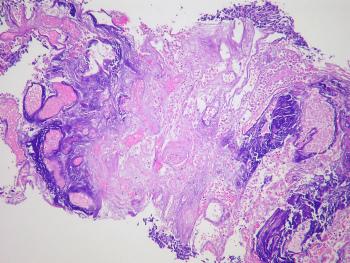

Слизистая аденокарцинома кишечника

Этот вид опухоли по распространенности занимает вторую позицию среди других раковых заболеваний кишечника. В состав опухоли входят патологические железистые клетки, которые продуцируют большое количество слизи. Онкологи говорят о развитии слизистой аденокарциномы, когда более 50% опухолевых клеток продуцируют слизь. По сравнению с обычной аденокарциномой слизистый тип опухоли сложнее лечится. Противоопухолевая терапия проводится комплексно, включает несколько эффективных методик.